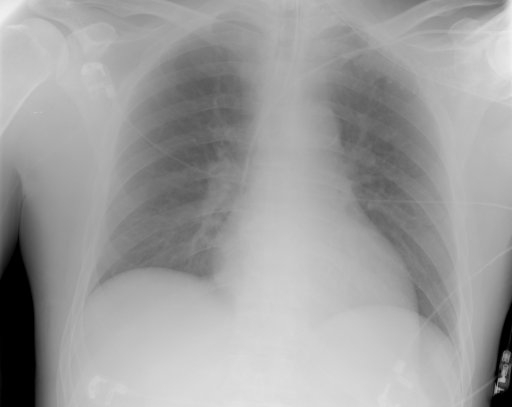

The IRMA dataset, supplied for the imageCLEF organization, had annotated codes were similar to domain expert knowledge [9, 12, 13, 14]. This database has been used by many researchers and is comprised of preset test and training portions, which enable direct comparisons of metrics. The IRMA codes (manually created by several clinicians) contains information on technical, biological and diagnostic traits of the image in a structured manner: TTTT-DDD-AAA-BBB. Each section is hierarchical meaning there is a least significant bit and most significant digit (Table 1). Sample IRMA images are depicted in Fig. 1.